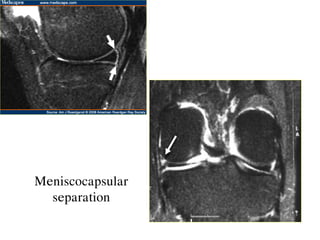

o Meniscocapsular separation

Meniscocapsular

separation

MRI giuùp xaùcñònh vò trí suïn raùch vaø daïng ñöôøng raùch: - Vò trí raùch suïn: 1/3 trong, giöõa hay ngoaøi - Daïng raùch: o Horizontal tear o Longitudinal tear o Radial tear o Flap tear o Bucket handle tear o Meniscocapsular separation